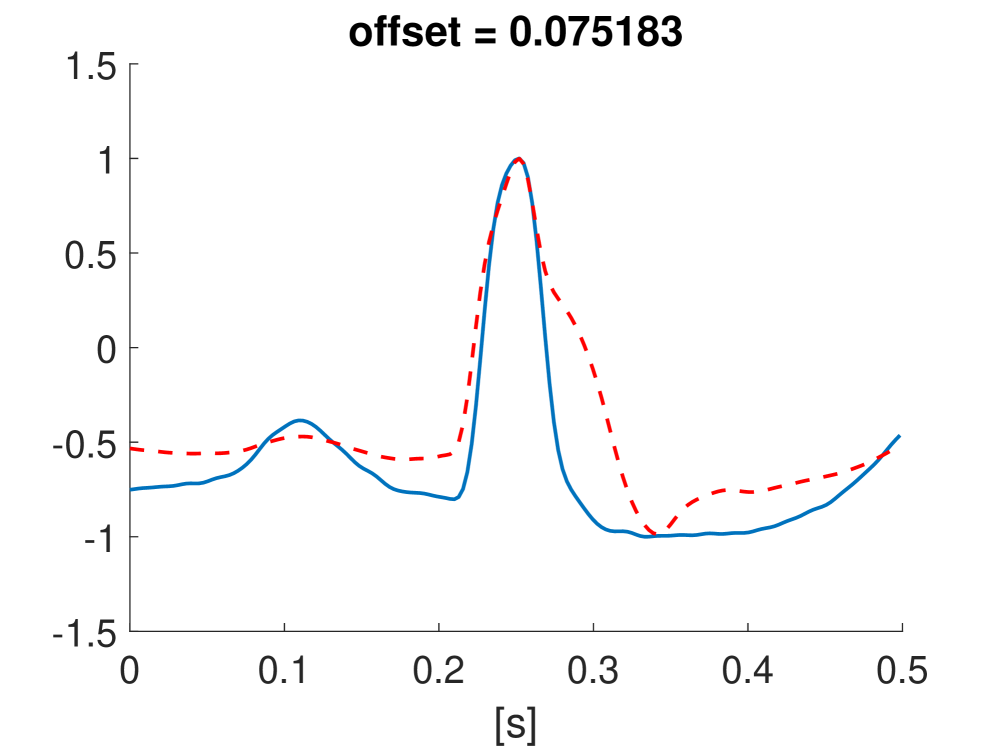

Fig. 10 shows the result in input space of moving along the first principal components in the latent feature space. As original base point we take a normal beat signal, i.e. corresponding to a hidden unit on the bottom right of Fig. 9(a). The smooth transition between the beat patterns allows for interpretation of the first principal components. This allows a clinical expert to understand on what basis the paced beats are separated by the principal components and if this basis has a physiological meaning. In order to investigate the separated region of the latent space at the top of Fig. 9(b) we start from a paced beat pattern and vary along the third principal component. This allows us to see which sort of heartbeat patterns are responsible for this specific distribution in the latent space.